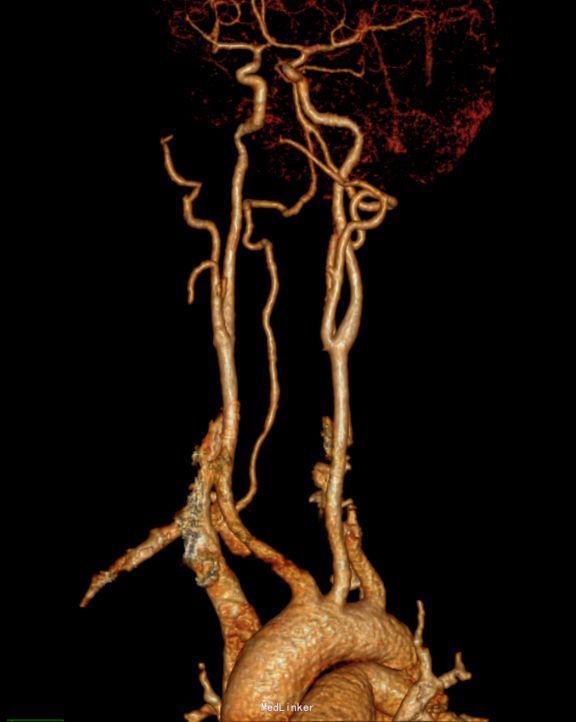

肺功能报告:MMEF轻度下降,V25中度下降,VE>10L。患者存在小气道气流轻度受限,过度通气,肺功能稍受损。 CT胸部增强扫描:右侧胸腔顶部见一大小约4.3*3.4cm软组织密度肿块,边界清楚,边缘光滑,与脊柱呈宽基底相连,增强后肿块明显均匀强化。第三肋骨可见致密结节影。意见:1、右后上纵隔占位,多系肿瘤:神经源性?淋巴源性或其他?2、心包及双侧胸膜稍增厚;3、右侧第3肋腋段致密结节,考虑骨岛可能。

诊断:1、 纵隔肿瘤(右后上,神经源性?淋巴源性?)2、脂肪肝3、脾大4、右第三肋骨骨岛形成5、右上颌窦囊肿 在全麻下右开胸右后上纵隔肿瘤切除术。术中见:1)胸内淡黄色积液50ml,无粘连;2)胸膜无种植;肿瘤对肺叶无侵犯, 肿瘤对心包无侵犯。3)肿瘤位于右后上纵隔约 4*3*3cm大小、包膜完整。4)淋巴结肿大及侵犯情况:无 5)术中冰冻结果:梭形细胞肿瘤,倾向神经源性 。6)术中特殊情况:无 完整切除肿瘤,术中出血不多,未输血,术后患者安返病房,给予对症、支持治疗。